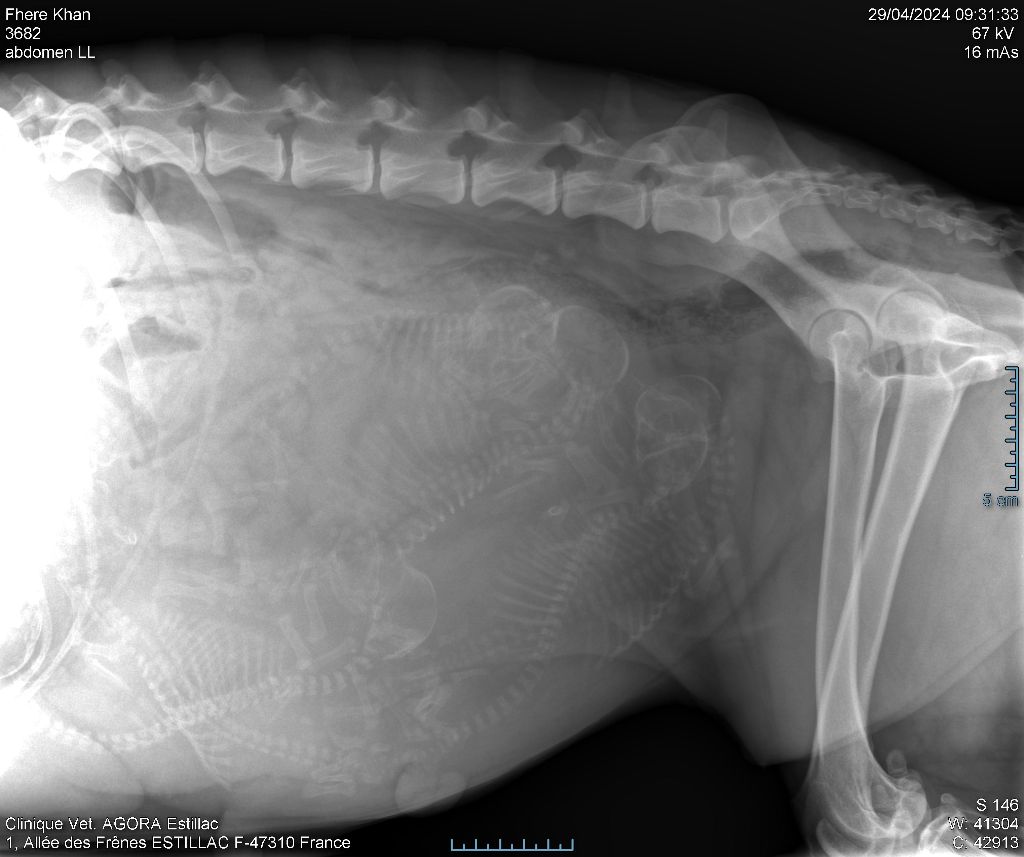

2024 - Les 8 nains de Shere Khan :) Le lendemain de la mise bas Les 8 chiots, 4 femelles 4 males 5 jours avant ;) Même le papa s'occupe de sa progéniture :) Le matin de la mise bas, 9h12, le 1er chiot à naitre. La 1ere sortie femelle fauve collier orange - 9h19 Le 2eme est né - male bringé collier violet - 10h12 Le 3eme est né - male bringé collier bleu - 11h29 Le 4eme est en train de naitre, tout se passe bien. Toujours le 4eme tout juste sortie de sa poche. Le 4eme - male bringé collier marron né à 12h10 18h36 - il y en a 7, au repos après avoir tous tété. 18h30 certainement la fin, le véto avait dit 6 voir 7 :) Shere Khan - une très bonne maman. Radiographie 5 jours avant à la clinique Le vétérinaire en voit 6 voir peut-être 7. 18h50 - Arrivée d'un 8eme. Femelle bringée elle aura le collier jaune Taïko le papa participe ;) Cuvée 2024 Ultime la demi soeur participe aussi :) Une affaire de Famille! On apprend à laper, c'est plus long :) C'est meilleur direct à la tireuse :) On attaque la 4eme semaine ! On est trimballé, maison, remorque, parc :( mais on mange bien :) Maman n'est jamais tès loin :) Notre demi soeur s'occupe de nous aussi. Sous surveillance de Papa :) Notre maître ne fait pas que ramasser nos crottes, il joue aussi :) 4eme semaine avec Maman Papa et notre grande Soeur Ultime :) Notre grande demi-soeur, on l'appelle Tim, c'est plus court. Papa adore faire la vaisselle :) Notre maître passe sa journée à nous compter :) D'ailleur il en manque un, il a du partir en douce, on a rien vu :) Sous la surveillance de Taïko notre Père, attention :) Après une bonne tétée, la sieste avec Maman s'impose :) Voila la pesée, plus de 16,5 kg à nous 8 :) Va falloir trouver mieux que la gamelle pour nous peser :( Atterissage sur le nez. Elle tient pas ta gamelle ! Bhé si ça tient, c'est juste qu'il faut pas bouger :) C'est encore moi le plus gros :) Ma grande soeur m'adore. Elle est super forte :) On peut pas être tranquille :( Tu veux ma photo ?! C'est la récré ! :) Notre grande soeur est top cool! 1, 2, 3, 4, 5, 6, 7, .... il en manque encore un ? Hè j'suis pas en bois ! Patée d'annif, on a 1 mois ! 1, 2, 3, 4, 5, 6, 7, 8. 1, 2, 3, 4, 5, 6, 7, 8. 1, 2, 3, 4, 5, 6, 7, 8. c'est bon ils sont tous là :) Taïko toujours de corvée de vaisselle :) Elle est belle ma Shere Khan! Pesé collier bleu 4630g Pesée collier blanc 4430g Pesée collier orange 4030g Pesé collier violet 4930g Pesée collier rouge 4230g Pesée collier noir 4430g Pesée collier marron 4730g Pesée collier jaune 4430g Sortie quotidienne en famille :)